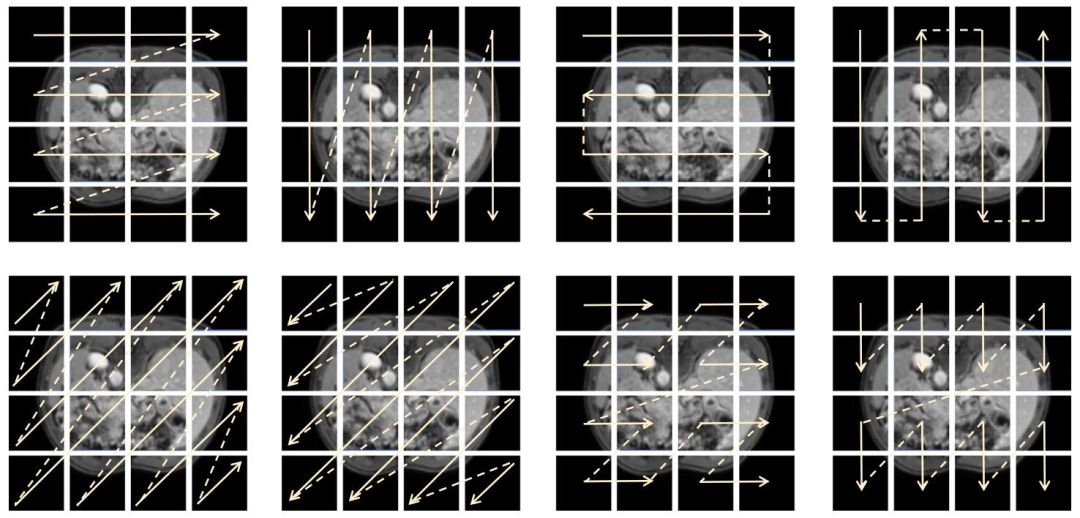

Fig. 4. Visualization of the scan head load distribution within a single SwitchVSSBlock of our Switch-UMamba. This visualization corresponds to the resultsobtained from the Abdomen MRI dataset.

图4 Switch-UMamba模型单个Switch VSS块内扫描头负载分布可视化 该可视化结果对应于腹部MRI数据集上所得结果。